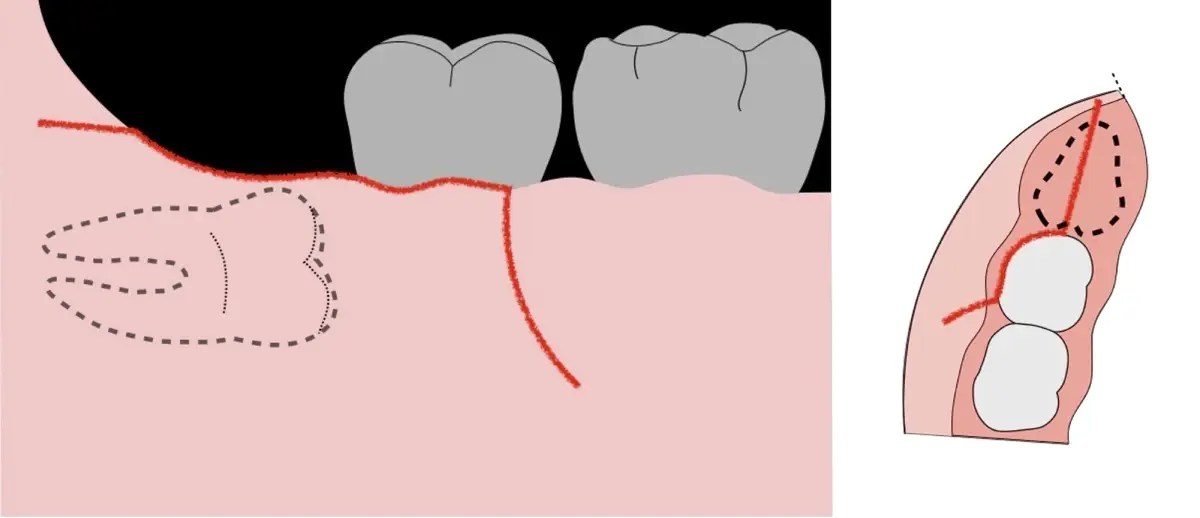

Figura 3. Decolado a espesor total para el acceso a la tercera molar.

Figura 4. Demarcación de la zona de osteotomía con insertos de corte recto y/o angulado a nivel oclusal. Vista frontal (a). Vista oclusal (b).